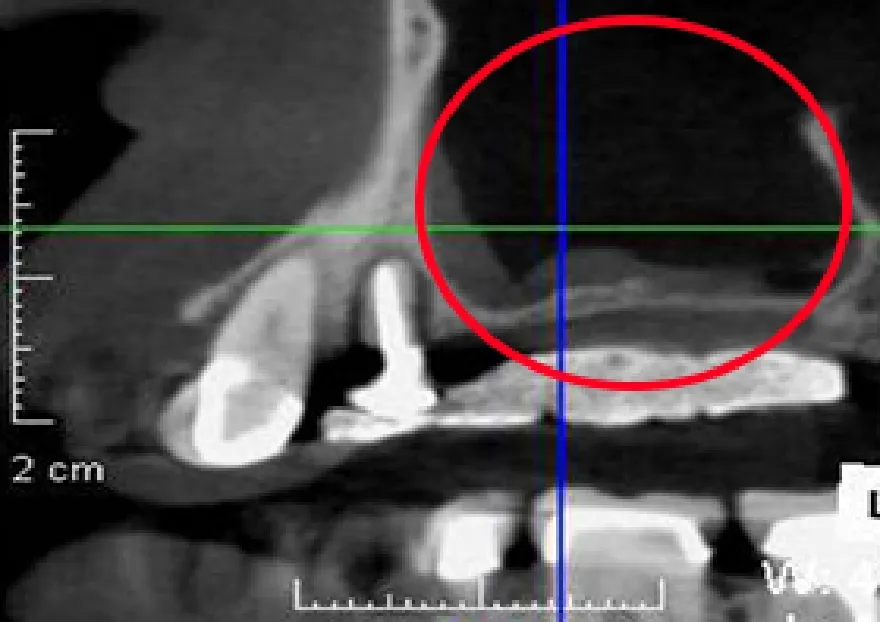

• 上顎の骨がほとんど無い状態です。

• サイナスリフトという骨再生手術で、十分な骨が出来ているのが分かります

サイナスリフト

上顎のインプラント治療の際に骨の高さが足りないケースで、上顎洞という骨内の空洞を利用して骨を作る手術です。